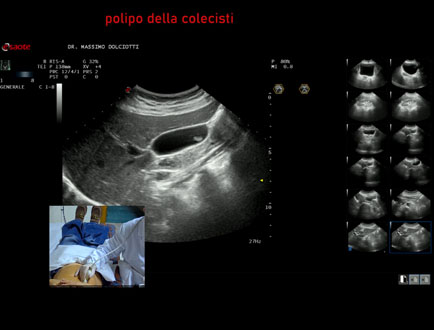

Data inserimento: 31/03/2025

Ecografia del: 24/03/2025

Strumento: Esaote MyLab Eight

Sonda: Convex Multifrequenza 1-8 MHz

Età Paziente: F 57 anni

Motivazione dell'esame: follow up per polipo della colecisti.

Commento all'esame: le immagini ed il video documentano la colecisti parzialmente distesa, con evidenza al corpo della colecisti di immagine isoecogena, delle dimensioni di 10,2 - 11,8 mm, non mobile con il decubito, senza rilievo di vascolarizzazione, da ricondurre, come prima ipotesi, a polipo adenomatoso della colecisti.

Conclusioni: polipo adenomatoso della colecisti (adenomatous polyp of the gallbladder).

Presentazione: Dr. Massimo Dolciotti - Ancona